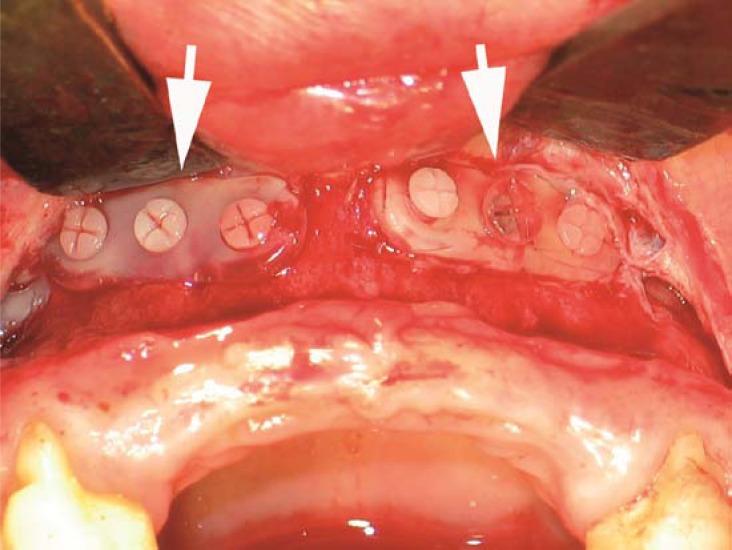

The fatigue performance of explanted in-situ degraded osteofixations/osteosyntheses, fabricated from poly (70L-lactide-co-24DL-lactide-6-trimethylane-carbonate or PLDLLA-TMC) copolymer was compared to that of virgin products. The fatigue test was performed on 21 explants retrieved from 12 women and 6 men; 16-46 years by a custom-designed three-point bend apparatus using a staircase method and a specified failure criterion (an increase of the deflection of the specimen > 1 mm) with run-out designated as "no failure" after 150,000 loading cycles. While all the virgin products showed run-out at 38N, all of the specimens fabricated from explants failed at this load level. For the explant specimens, although there was a trend of decreased failure load with increased in-situ time, this decrease was pronounced after 4 months in-situ, however, not yet statistically significant, while a 6-month in-situ explant had significantly less failure load. Three and four month in-situ explants had highly significant differences in failure load between measurements close and distant to the osteotomy line: p=0.0017 (the region of maximum load in-situ). In the virgin products, there were only traces of melt joining and cooling, left from a stage in the manufacturing process. For the implants retrieved after 4.5 months in-situ, the fracture surfaces showed signs of degradation of the implants, possibly caused by hydrolysis, and for those retrieved after 9 months in-situ, there were cracks and pores. Thus, the morphological results are consistent with those obtained in the fatigue test. The present results suggest that resorbable osteofixations fabricated from PLDLLA-TMC are stable enough to allow loading of the healing bone and degrade reliably.

将由聚(70L-丙交酯-co-24DL-丙交酯-6-三甲基碳酸酯或PLDLLA-TMC)共聚物制成的取出的原位降解骨固定物/骨合成物的疲劳性能与原始产品进行了比较。对从12名女性和6名男性(年龄16 - 46岁)身上取出的21个植入物进行了疲劳测试;使用定制的三点弯曲装置,采用阶梯法和指定的失效标准(试样挠度增加>1mm),在150,000次加载循环后,将未失效指定为“无失效”。虽然所有原始产品在38N时均未失效,但所有由取出的植入物制成的试样在此载荷水平下均失效。对于取出的植入物试样,尽管存在随着原位时间增加失效载荷降低的趋势,但这种降低在原位4个月后才明显,不过尚未具有统计学意义,而原位6个月的取出植入物的失效载荷明显更低。原位3个月和4个月的取出植入物在靠近和远离截骨线处的测量失效载荷存在高度显著差异:p = 0.0017(原位最大载荷区域)。在原始产品中,仅留有制造过程中一个阶段的微量熔体连接和冷却痕迹。对于原位4.5个月后取出的植入物,断裂表面显示出植入物降解的迹象,可能是由水解引起的,而对于原位9个月后取出的植入物,则存在裂缝和孔隙。因此,形态学结果与疲劳测试中获得的结果一致。目前的结果表明,由PLDLLA-TMC制成的可吸收骨固定物足够稳定,能够承受愈合骨骼的负荷并可靠地降解。